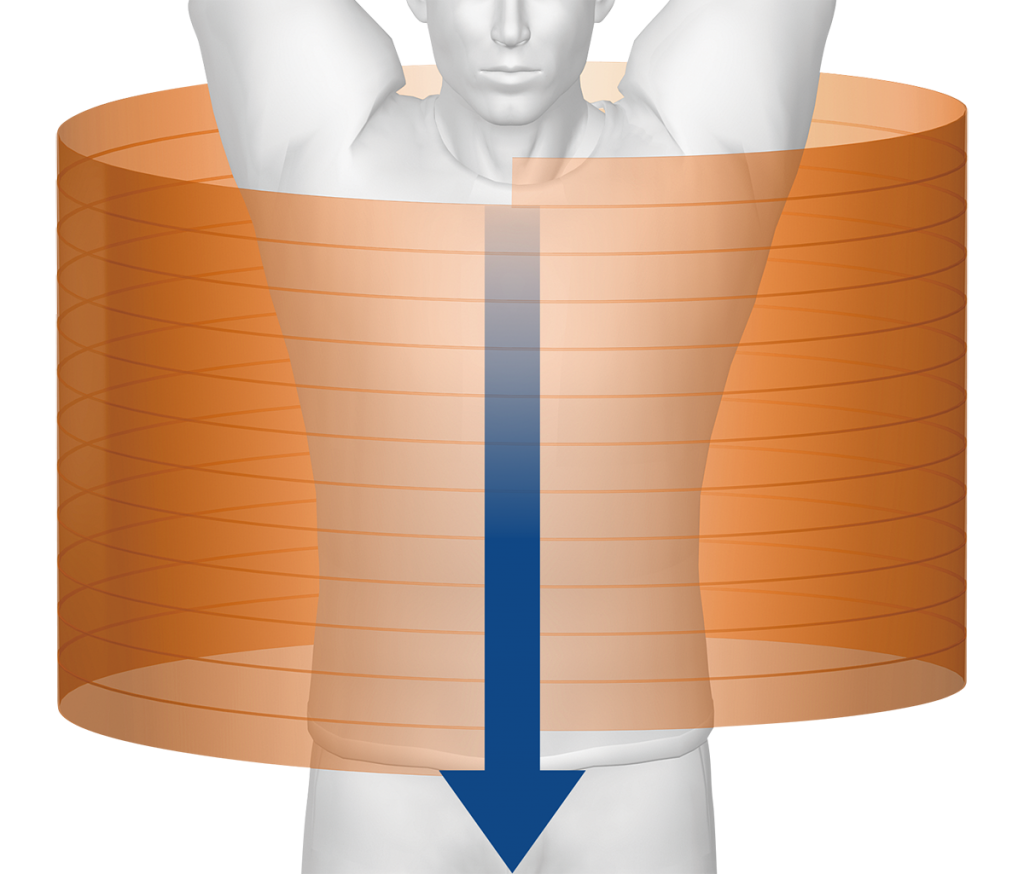

Компьютерный томограф Aquilion Lightning 80 Canon укомплектован детектором с полем охвата 20 мм, что предоставляет исследователю новые клинические возможности. Мощный генератор рентгеновских лучей, апертура гентри 780 мм и минимальная высота стола 32 см с функцией механизированного перемещения влево-вправо на 42 см предоставляют возможность проводить обследование даже очень полных пациентов. Современная рентгеновская трубка обладает существенной интенсивностью охлаждения, что позволяет осуществлять непрерывно даже самые сложные и длительные манипуляции.

SURE Exposure ™ 3D

Это полностью интегрированное автоматическое управление экспозицией обеспечивает оптимальное качество изображения и дозу пациента.

3 фазы vHP

Уникальный режим сканирования Toshiba, который позволяет получить одиночный спиральный захват с плавной сменой спирального тона. 3 клинически адаптированных настройки высоты тона могут использоваться в пределах одного спирального сканирования.

Эксклюзивная технология Toshiba Medical, адаптивный диагностический инструмент с переменным шагом спирали VHP позволит сканировать несколько сосудистых территорий в пределах одной задержки дыхания и одной контрастной инъекции.